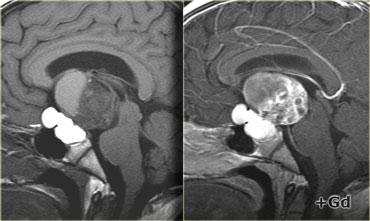

Trên các hình ảnh chuỗi xung T1W mặt phẳng đứng dọc không và có tiêm thuốc tương phản từ, có thể nhận thấy tuyến yên bị chèn ép.

Có một khối lớn trong hố yên và trên hố yên với các thành phần dạng nang, thành phần ngấm thuốc cũng như vôi hóa.

Các dấu hiệu này ở trẻ em gần như là đặc trưng bệnh lý của sọ hầu u (có thể chỉ cần chẩn đoán phân biệt với u bì – dermoid).